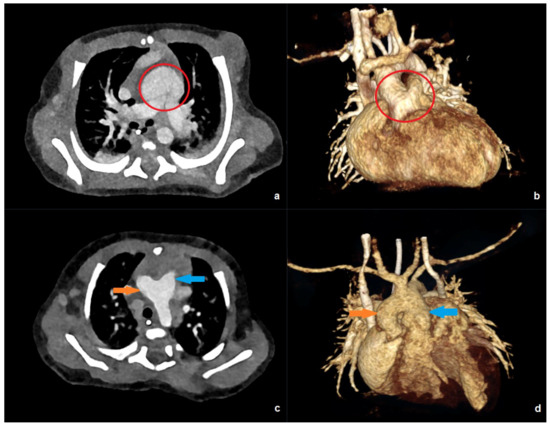

Photon-Counting CT Enables Higher Image Quality at a Lower Radiation Dose Compared with a 256-Slice Energy-Integrating Detector CT in Pediatric Patients with Congenital Heart Disease

Background/Objectives: There is an increasing need for cross-sectional imaging in pediatric patients with congenital heart disease. This patient group is highly sensitive to ionizing radiation. The purpose of this article was to evaluate differences in radiation dose and image quality between a first-generation photon-counting (PC)-CT system and a 256-slice single-source energy-integrating detector (EID)-CT in these patients. Methods: We retrospectively assessed effective dose, CT dose index-volume (CTDIvol), dose length product (DLP), and image quality of all prospectively electrocardiography-gated CTs of the thorax in all patients < 18 years of age examined between February 2021 and August 2024 (n = 43). Two independent observers subjectively scored image quality, vascular contrast, and noise on a 5-point Likert scale. In addition, we assessed the signal-to-noise-ratio (SNR) and contrast-to-noise-ratio (CNR) quantitatively. Results: All dose parameters were significantly lower in the PC-CT (n = 27) versus the EID-CT (n = 16) group (mean effective dose: 0.8 ± 0.64 versus 2.2 ± 0.88 mSv, p < 0.001; mean CTDIvol: 1.22 ± 0.96 versus 4.8 ± 1.08 mGy, p < 0.001; mean DLP: 30.7 ± 31.9 versus 73.7 ± 50.7 mGy*cm, p < 0.001). Overall subjective image quality and contrast were rated higher in the PC-CT group (p = 0.046 and < 0.001, respectively). Quantitative CNR was significantly higher in the PC-CT group (mean 39.1 ± 12.9 versus 26.2 ± 10.8, p = 0.002). Conclusions: PC-CT enables high-quality examinations for the evaluation of congenital heart disease with a highly significant dose reduction compared with a 256-slice single-source EID-CT. Full article